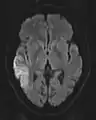

DWI showing restricted diffusion in the medial dorsal thalami consistent with Wernicke encephalopathy